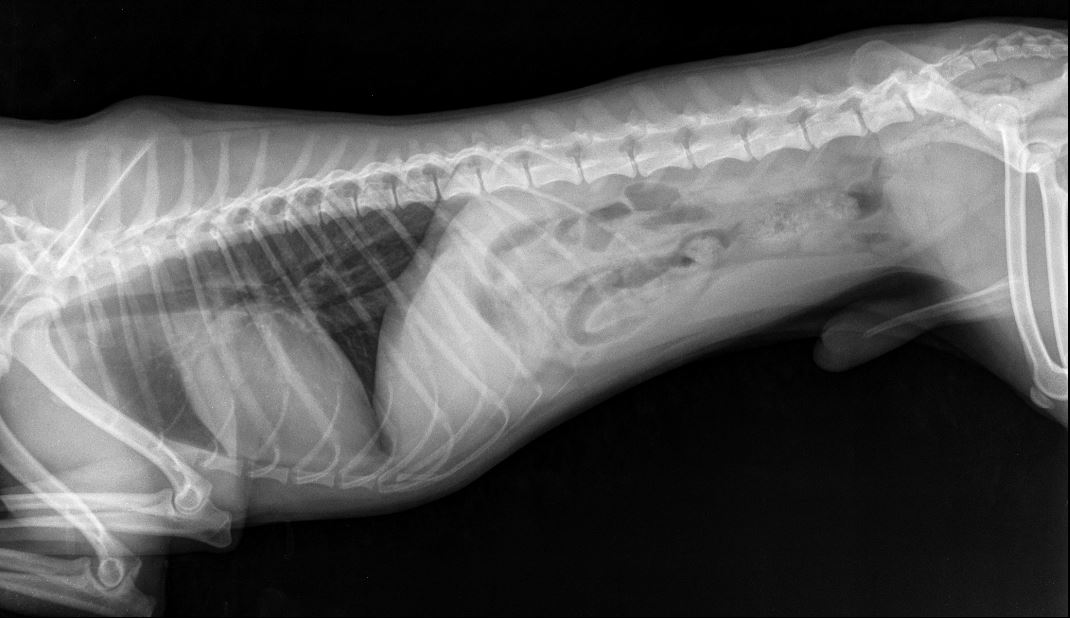

Прикладываю снимки, приблизила, чтобы лучше видно было. Также выкладываю снимок грудной клетки(этот снимок мы делали пару месяцев назад, когда он кашлял и врач исключал бронхит), на нем тоже есть ТБС, вдруг тоже на нем что-нибудь видно..

Снимки:

Миниатюры

Нажмите на изображение для увеличения

Название: 04.02.2018 Джин КС (увеличение с общего снимка).JPG

Просмотров: 811

Размер:	66.7 Кб

ID:	90392   Нажмите на изображение для увеличения

Название: 04.02.2018 Джин общий снимок.JPG

Просмотров: 736

Размер:	31.1 Кб

ID:	90393   Нажмите на изображение для увеличения

А где вы вывих тбс видите на снимках? И какой связки там нет?

В том то и дело, что я вывиха не вижу... Потому и сомневаюсь... пересмотрела наверное больше сотни разных снимков собак с вывихами, дисплазиями и другой ерундой, но на нашем снимке головка бедренной кости находится в вертлужной впадине, никаких наростов на ней нет, сама вертлужная впадина выглядит как глубокая чашка, а не как блюдце (которое описывают при дисплазии).. Потому и сомнения:(((

По сабжу. Переделывайте рентген - собака лежит как черти что. Должна лежать прямо. Конечности должны быть строго параллельны, рентген ТБС делается с оттяжкой. Тогда можно будет говорить о корректных снимках (и только о них). О каких связках речь, если они на рентгене не видны? Для того, чтобы разглядеть связки вообще - делают КТ либо МРТ.

именно вывих, но коленной чашечки.

Даже при этой раскладке явно видно, что вывиха тбс нет.